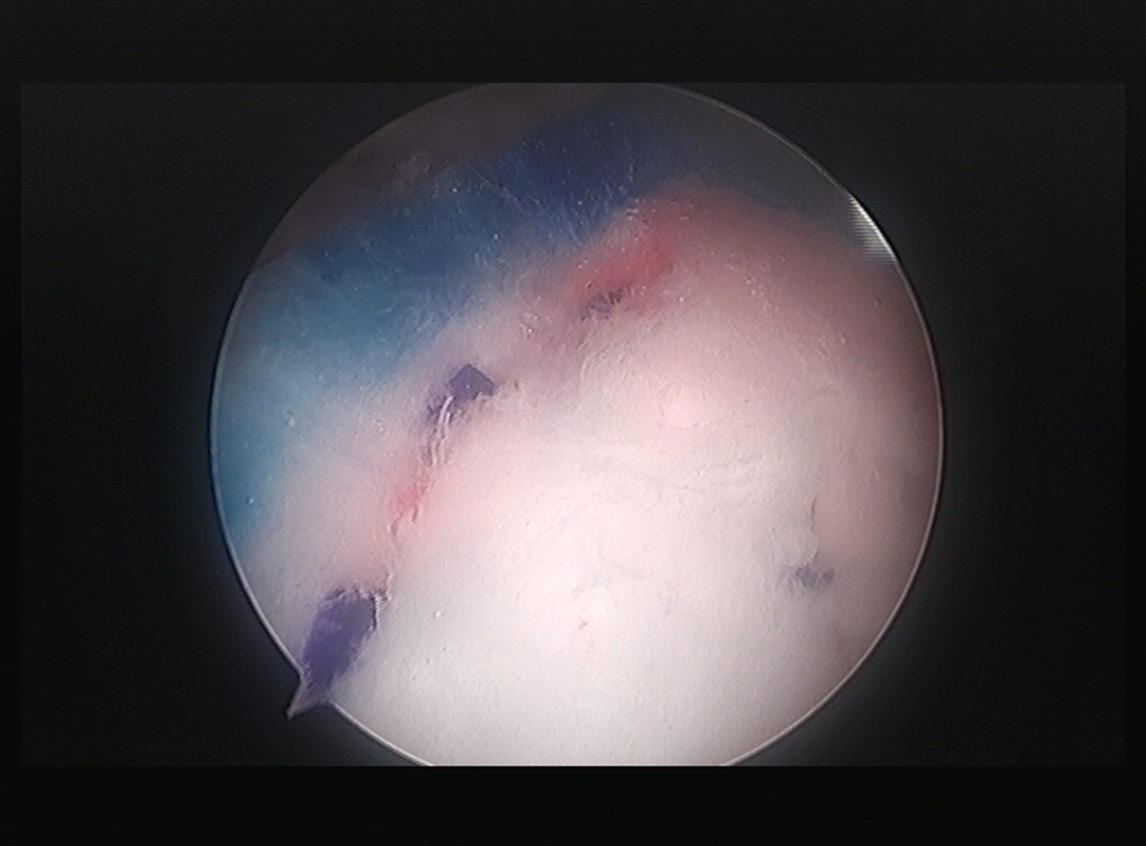

10주 후 초음파:

봉합 부위가 정상 인대처럼 하얗게 재생되어 있었습니다. 골수자극의 효과로 예상보다 빠른 재생이 확인되었습니다.